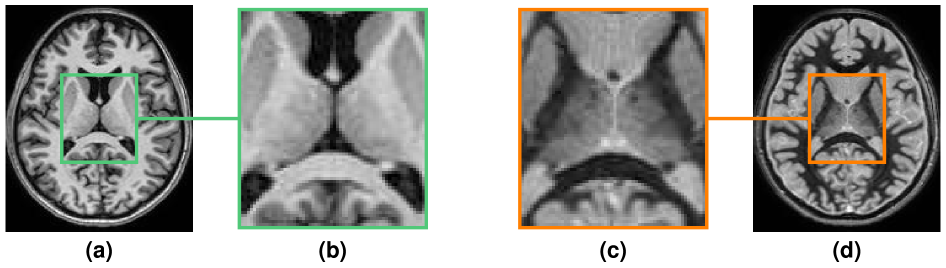

Visualization of subcortical structures using magnetic resonance (MR) imaging is important for understanding the causes and progression of various diseases [1] and for planning and assessing the efficacy of their treatment [2]. Most imaging protocols used to image the thalamus, its nuclei, the basal ganglia, and related cortical networks require special pulse sequences such as quantitative susceptibility mapping (QSM) [3] and fast gray matter acquisition T1 inversion recovery (FGATIR) [4] or specialized hardware such as 7T scanners [5]. White matter nulled (WMn) T1-weighted (T1-w) imaging, such as the FGATIR image shown in Fig. 1(d), is often used in surgical planning for deep brain stimulation (DBS) [2] and is employed in some automatic methods for segmentation of thalamic nuclei [6, 7]. Despite its increasing usage in clinical protocols, FGATIR is not yet part of many widely used neuroimaging datasets, such as OASIS [8] and ADNI [9]; this gap motivated us to explore synthetic generation of FGATIR images. In this paper, we present a new way to synthesize FGATIR images and to use these to help visualize and delineate thalamic nuclei and related structures using conventional clinical MR imaging.

Refer to caption

Figure 1: Resulting images from a 3D MPRAGE sequence with two different inversion times (TIs). (a) The cerebrospinal fluid nulled Magnetization Prepared Rapid Acquisition with Gradient Echo (MPRAGE) sequence which is the same sequence with a TI of 1,200ms and (d) a Fast Gray Matter Acquisition T1 Inversion Recovery (FGATIR) sequence with a TI of 400ms. Shown in (b) and (c) are zoomed versions of (a) and (d), respectively, that are focused on the thalamus. The conventional long TI, MPRAGE image shows relatively poor contrast between thalamic nuclei, whereas the short TI, FGATIR images have sufficient contrast to visualize and segment these structures.

The 3D magnetization prepared rapid acquisition with gradient echo (MPRAGE) image [10] is routinely acquired in neuroimaging, largely because of its excellent gray matter (GM)/white matter (WM) contrast as well as its fast acquisition time and high resolution. It is conventionally acquired to yield a T1-w contrast using a 180180^{\circ} inversion pulse and an inversion time (TI) that will null the signal from cerebrospinal fluid, as shown in Fig. 1(a). The FGATIR pulse sequence is a 3D MPRAGE sequence with a much shorter TI (typically around 400 ms at 3T), which is selected to approximately null the WM signal. Although a conventional MPRAGE image shows relatively poor contrast of the thalamic nuclei, striatum, globus pallidus interna, nucleus accumbens, and internal capsule, FGATIR images provide improved contrast relative to MPRAGE for the visualization and/or segmentation of these critical brain structures [4].